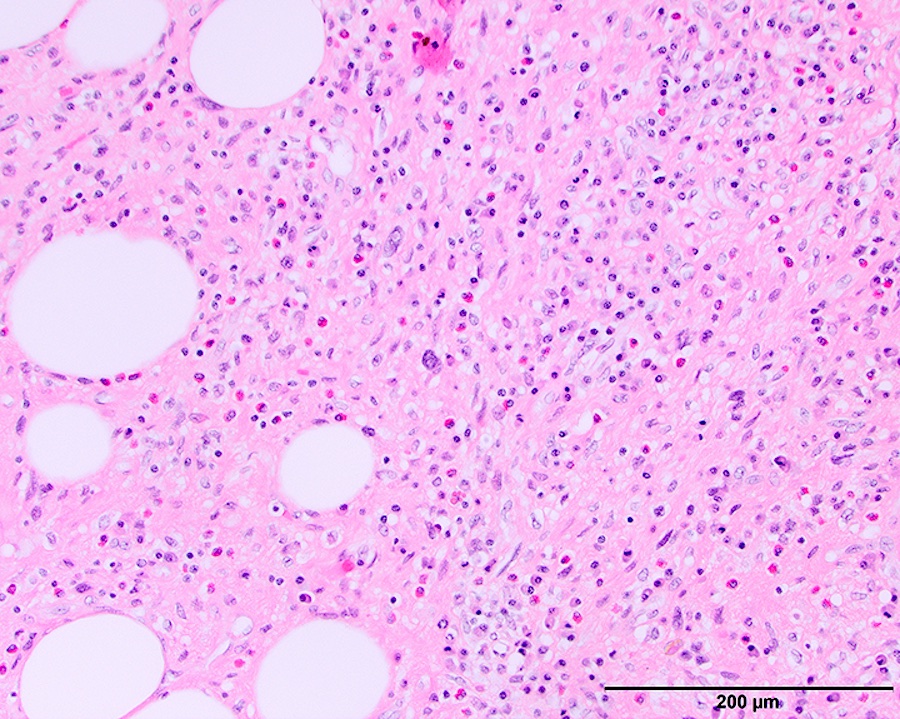

Microscopic (histologic) images

Contributed by Michael Clay, M.D., Melanie Bourgeau, M.D. and AFIP

Morphologic variability:

Microscopic (histologic) description

- Depends on subtype, generally composed of mature fat with variably sized adipocytes and bands of fibrotic stroma containing spindle cells with enlarged, hyperchromatic nuclei

- Can be markedly atypical

- Cellularity is low and mitotic figures are uncommon

- Atypical cells are more commonly found in fibrous septa and in a perivascular distribution

- Sclerosing subtype

- Second most common subtype

- Predilection for retroperitoneal or paratesticular location

- Collagenous fibrous tissue with scattered adipocytes and atypical multinucleated stromal cells

- Scant lipogenic component may be missed in small samples